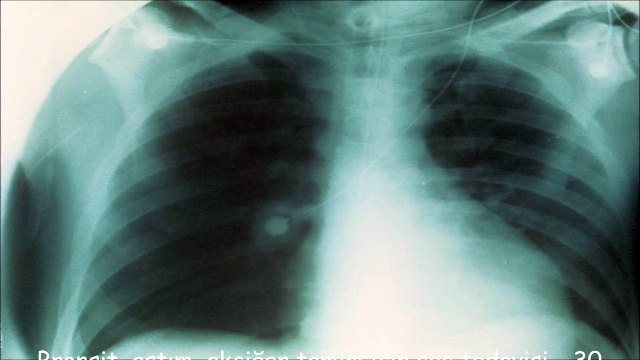

Akciğer Hastalıkları Uzmanı Prof. Dr. Turhan Ece astım hastalığı hakkında bilgi veriyor. (Bedenimizdeki Ayetler programı, 10. bölümden) Bu programda Prof. Dr. Turhan Ece; nefes darlığı, solunum, alerji, koah, alerjik rinit, alerji testi, astım, polen, immünoterapi, sinüsler, burun, solunum sistemi, mast hücresi, bronş kasları, mukoza, göğüste sıkışma, astım krizi, astım tedavisi, astım ilacı, bronkoskopi konuları ile ilgili bilgi veriyor. a9.com.tr/izle/208943/Belgesellerden-Secme-Bolumler/Astim-Hastaliginin-Nedenleri-Belirtileri-ve-Tedavisi A9 uygulama mobil linkler : A9 TV iphone : itunes.apple.com/tr/app/a9-tv/id432879700 A9 Radyo iphone : itunes.apple.com/tr/app/a9-tv-radio/id929302730 A9 TV Android : play.google.com/store/apps/details?id=com.chelik.client.a9tv A9 Radyo Android: play.google.com/store/apps/details?id=com.chelik.clients.a9radyo